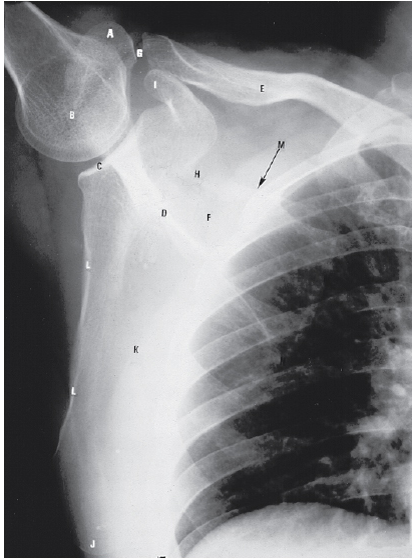

Which letter identifies the costal surface of the scapula?

C - K

The radiograph illustrates an AP projection of the scapula; abduction of the arm moves the scapula away from the rib cage, revealing a greater portion of the scapula than would be visualized with the arm at the side. A number of bony structures are identified: the acromion process (A), the humeral head (B), glenoid fossa (C), scapular spine (D), clavicle (E), supraspinatus fossa (F), acromioclavicular joint (G), scapular notch (H), coracoid process (I), inferior angle/apex (J), body/distal surface (K), lateral/axillary border (L), axillary part upper rib (M